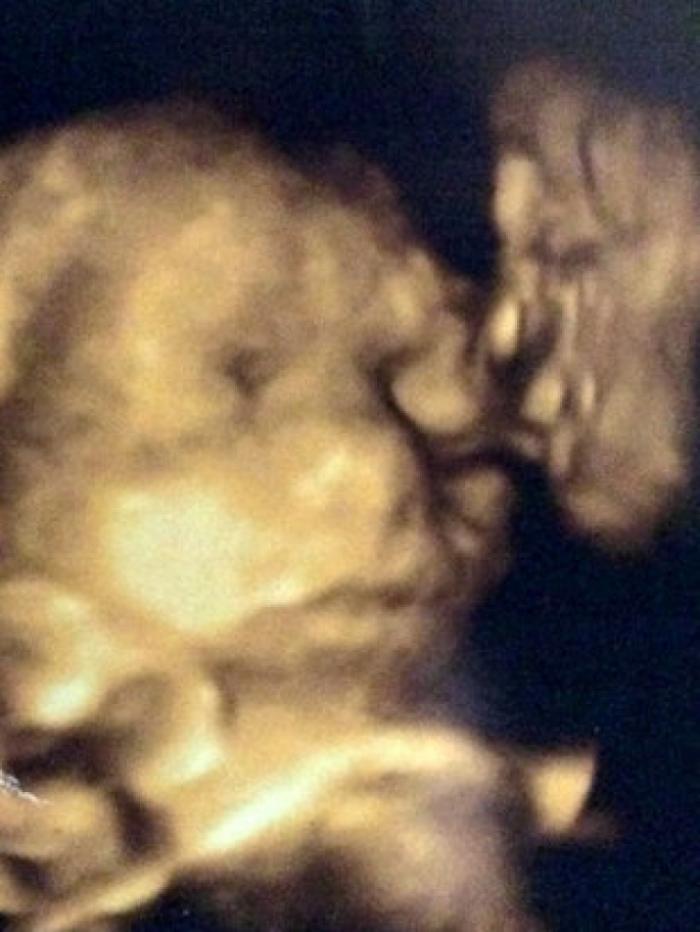

O femeie însărcinată a avut ȘOCUL vieții ei la ecografie! Cine îi săruta bebelușul din pântece

Jane Hornsby, o tânără de 21 de ani din SUA, a avut parte de șocul vieții ei după ce și-a făcut o ecografie 4D în timpul sarcinii. Tânăra a descoperit că, în colțul imaginii se afla bunicul său Jack, decedat în 2007.